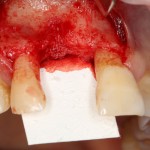

Если после этого BioGide намочить физраствором, им легко укрыть получившийся объем:

Для надежности можно зафиксировать пинами: